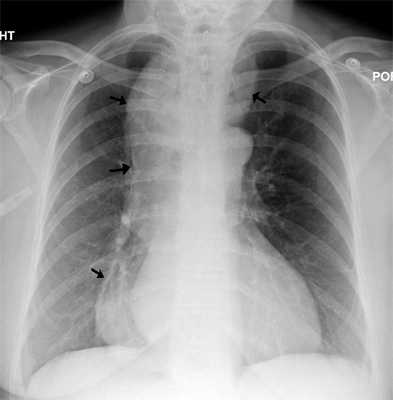

(Слева) На рентгенограмме в прямой проекции в положении пациента стоя визуализируется расширенный пищевод с конусообразным сужением просвета в виде «птичьего клюва» сразу же над областью перехода в желудок. Обратите внимание на отсутствие газового пузыря желудка и на границу между бариевой взвесью и жидкостью в просвете пищевода.

(Справа) На рентгенограмме визуализируется в значительной степени расширенный, извитой пищевод, выглядящий как сигмовидная кишка: этот пример иллюстрирует последствия длительно существующей ахалазии нижнего пищеводного сфинктера. (Слева) На рентгенограмме органов грудной клетки в прямой проекции в вертикальном положении, полученной у женщины 28 лет с жалобами на недавно возникшее нарушение глотания и появление неприятного запаха изо рта, определяется отсутствие уровня «жидкость-газ» в просвете желудка.

(Справа) На рентгенограмме пищевода, выполненной при рентгеноскопии этой же пациентке, определяется выраженное расширение просвета пищевода с наличием сужения и деформации в его дистальных отделах в виде «птичьего клюва».